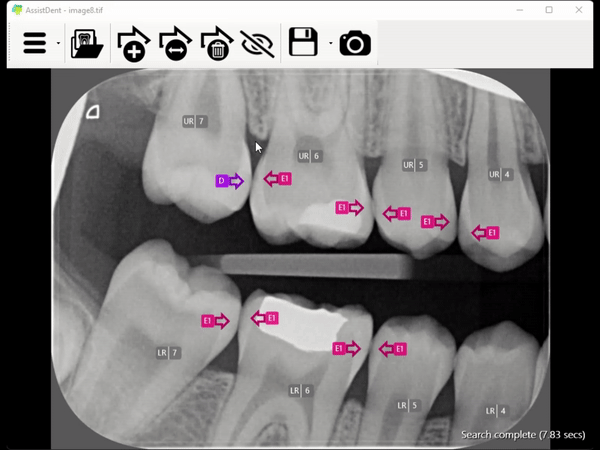

What does AssistDent do?

Dentists everywhere are putting more emphasis on preventive treatment and minimum intervention. But in the case of enamel-only proximal caries, early-stage identification is not proving easy.

If detected early, the disease can be reversed by non-invasive means – but the subtle patterns on bitewing radiographs that represent demineralisation are hard to spot and all too often are missed.

AssistDent, launched in 2019 and incorporating advanced machine learning algorithms, has been developed to tackle the bitewing challenge head on – and has subsequently been proven to do its job extremely effectively.

A recent study of practicing dentists assessing bitewings for enamel-only proximal caries showed they achieved a 76% detection rate when prompted by AssistDent compared to 44% without AssistDent.